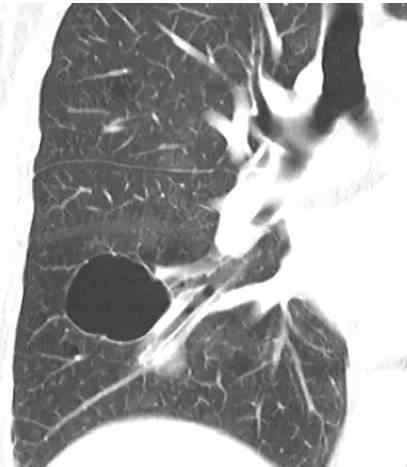

图2电脑断层显示肺囊肿

囊肿显示肺实质圆形透明或低密度区,与正常肺组织界限清楚。囊肿的壁厚各不相同,但通常很薄,没有肺气肿。肺中的囊肿通常含有空气体,但偶尔也会含有液体或固体物质。囊性变一词常用于描述淋巴管平滑肌瘤病或朗格罕氏细胞增生患者肺中扩大的薄壁含气腔,厚壁蜂窝状囊性病变见于终末期肺纤维化患者。